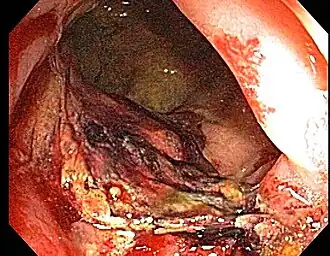

La « rectite» est le terme désignant les maladies se manifestant au niveau du rectum avec un processus inflammatoire et/ou infectieux aboutissant à d'éventuels ulcères, fistules et nécroses (dans les formes graves). Une rectite est parfois associée à une pathologie du côlon sigmoïde ou de l’anus) ou à une ou plusieurs maladies vénériennes[1],[2] dont la prévalence augmente dans le monde, surtout chez les adolescents et les adultes jeunes

Elle peut être ischémique et nécrosante et peut être source de septicémie[3] ou à une incontinence anale. Quand elle est accompagnée d’ulcérations rectales chroniques et/ou de rectorragies (éventuellement pluriquotidiennes) elle implique pour le patient des transfusions globulaires et/ou un traitement martial (complémentation de l'alimentation en fer bio assimilable). Le traitement curatif des rectites radiques chroniques hémorragiques s'est considérablement amélioré depuis les années 1990[4].

Il repose sur l'observation clinique et l'analyse de prélèvements en surface ou de biopsie (respectivement par écouvillonnage rectal et/ou biopsie rectale)[19] et il peut nécessiter une exploration endoscopique, par exemple pour une Rectite radique [20].

Une possibilité de cancer du rectum (bien que rare) doit être évoquée face à une rectite ulcérobourgeonnante[21].

Elle survient chez environ 5 à 10 % des malades ayant subi une irradiation pelvienne[23] en se manifestant généralement durant les deux premières années suivant l’irradiation[18], avec l'apparition d'un syndrome rectal et/ou de rectorragies (dans 1/3 des cas[23]).

Des rectorragies suivent l'apparition de télangiectasies et/ou d'une néo-vascularisation de la muqueuse rectale.

Ces rectites radiques pouvaient être traitées par électrocoagulation bipolaire et surtout par photocoagulation laser avec une efficacité proche de 80 %[30],[31] mais le matériel laser est coûteux et nécessite une bonne expérience tout en n’étant pas dénué de risques. L'électrocoagulation monopolaire endoscopique par plasma d'argon (APC) se fait sans contact avec le tissu traité (via un courant de haute fréquence appliqué au moyen d'un gaz argon ionisé) et il permet d’accéder à des lésions physiquement peu accessibles. Sa pénétration tissulaire réduite à 3 mm limite les risques de perforation[32], sans montée de température à 100 °C comme dans l’électrocoagulation. Parfois (rarement) une sténose rectale (rétrécissement) est constatée après le traitement[33].